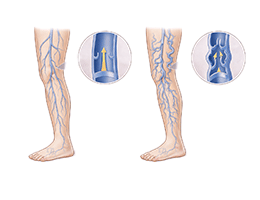

하지정맥류 (Varicose Veins)

심부정맥혈전증 (Deep Vein Thrombosis)